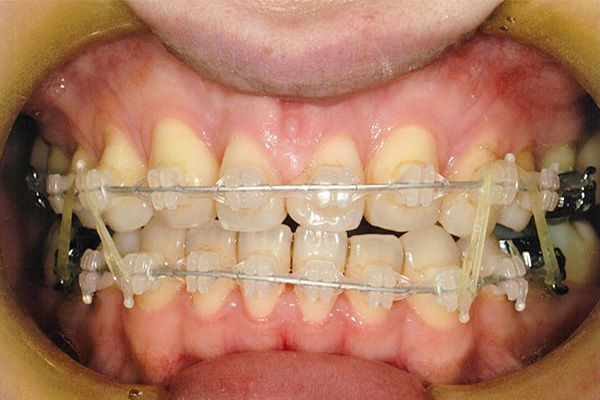

6ヶ月後